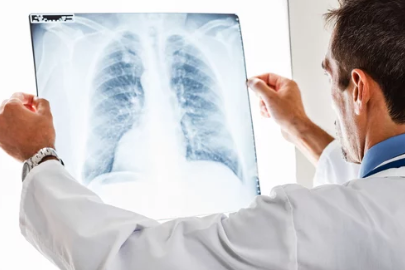

방사선 폐렴의 초기 증상은 다른 호흡기 질환과 유사하므로, 조기에 정확한 진단을 받는 것이 중요합니다.

- 의사 상담:

기침, 흉통, 호흡 곤란 같은 증상이 나타나면 즉시 담당 의사와 상담하세요. - 정기적인 폐 기능 검사:

방사선 치료 후 일정 기간 동안 폐 기능을 모니터링하고, 변화가 감지되면 바로 치료를 시작해야 합니다. - 약물 치료: